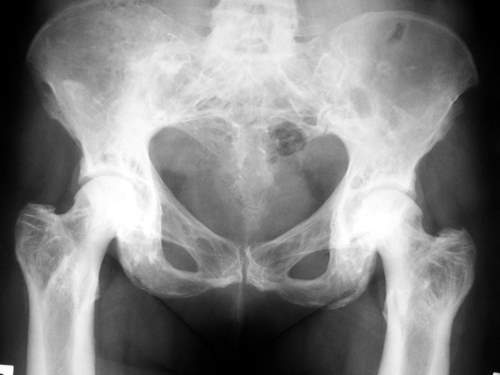

Гипертрофические явления в скелете возникают у легкоатлетов, спортивных игроков, гимнастов и прыгунов в воду в тазовой зоне таза в виде незначительного трансформации вертлюжной впадины. Дискометатели имеют утолщение дистального конца диафизарной части бедренной кости. У бегунов возникает повышенное расширение большеберцовой кости в зоне бугристости и малоберцовой – в головочной зоне. Гипертрофия хоккеистов и борцов характеризуется увеличением ширины проксимальных эпифизарных частей костных структур голени. Выраженному трансформированию подвергаются позвоночные сегменты, позвонки становятся четырехугольной либо клиновидной формы. Первая отмечается в основном у пловцов. Вторая характеризуется клином, который суживается кпереди, свойственна для штангистов, гребцов и велосипедистов, а клином, который суживается кзади, — для борцов.